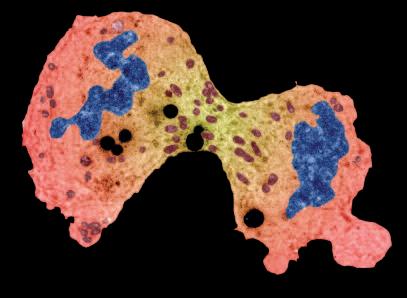

La pagina a fianco mostra l'immagine di una cellula tumorale reale, visualizzata al microscopio elettronico, che ingrandisce questa cellula 6500 volte rispetto alle sue normali dimensioni. Questo tipo di cellula prende il nome di carcinoma, cioè derivante da cellule epiteliali, il tipo di cellule che rivestono sia le superfici interne (polmoni, intestini) che esterne (pelle) del corpo.

Grazie a questo ingrandimento si possono identificare chiaramente alcune delle caratteristiche di tutte le cellule tumorali: a) l'enorme nucleo cellulare dalla forma insolita che spiega la loro grande capacità di riprodursi e b) la struttura non uniforme, complessa della superficie cellulare, che riflette una forte attività di secrezione di sostanze prodotte dalle cellule tumorali.

Una delle più importanti molecole secrete dalle cellule tumorali in grandi quantità sono gli enzimi a ‘forbice’ che digeriscono il collagene. Sono aggiunti graficamente a questa immagine, sotto forma di strutture simili ad un ‘pacman’ rosso.

Naturalmente questi sfere, nella vita reale, sono molecole biologiche, proteine, che hanno la capacità di tagliare le fibre di collagene e di altre molecole del tessuto connettivo. L‘immagine sopra mostra che non c’è un solo tipo di 'pacman' ovvero di queste molecole, ma

Digestione del tessut o connet tivo del tessuto connetti vo diversi tipi, quali il plasminogeno/plasmina e le metalloproteasi (strutture colorate tridimensionali). Queste molecole migliorano il loro effetto distruttivo attivandosi reciprocamente in forma di reazione a catena in cascata.